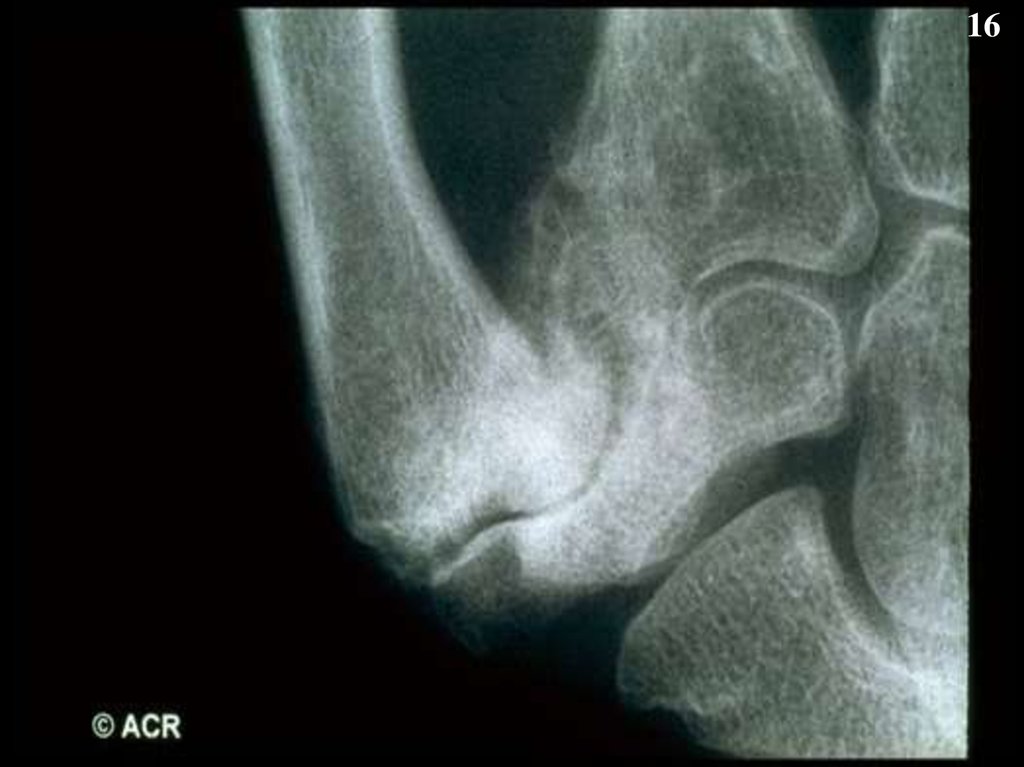

16.

16